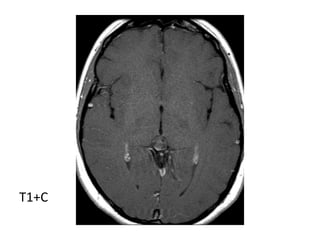

*T1+CApproximately 60% of lesions enhance

-Enhancement is usually thin (< 2mm) and

confined to the rim (either complete or

incomplete)

-It is important to note that if post contrast

imaging is delayed (60 - 90min), gadolinium

may diffuse into the cyst fluid and may lead

to the mass appearing solid

:

-T1+C : vivid and homogeneous

T1+C

*T1+C :

-Usually no enhancement

-Higher grade tumors tend to be larger and tend to

enhance more vividly

T1+C shows a slightly hypointense tectal mass which does not

enhance , the mass obstructs the aqueduct and is stable over

8 years

*T1+CApproximately 60% oflesions enhance -Enhancement is usually thin (< 2mm) and confined to the rim (either complete or incomplete) -It is important to note that if post contrast imaging is delayed (60 - 90min), gadolinium may diffuse into the cyst fluid and may lead to the mass appearing solid : -